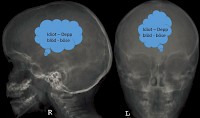

Gedanken röntgen!

Wenn man beim Röntgen Gedanken erkennen könnte? - Eine wahre Geschichte aus einer Kinderklinik.